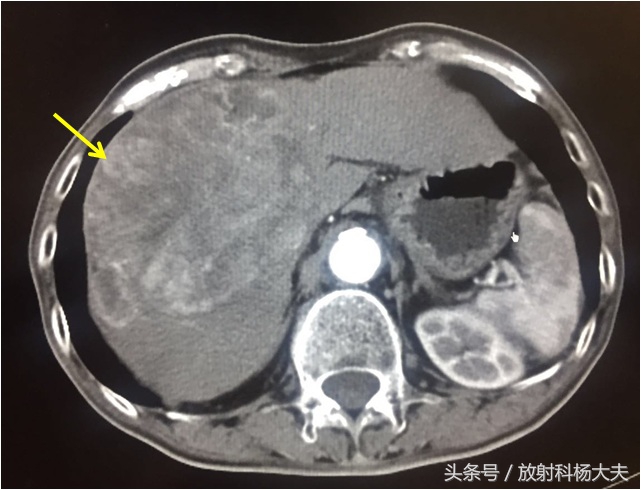

最近医院迎来了一波体检小高峰,体检结果也是几家欢喜几家愁。这是我碰到一位患者,男性,65岁,有乙肝病史。今年体检,查肿瘤标记物时发现AFP(甲胎蛋白)明显升高,做了增强CT,发现肝脏上了一个瘤子,通过影像学分析,可以肯定是肝癌!

黄箭为肝脏肿块,影像学为典型的肝癌